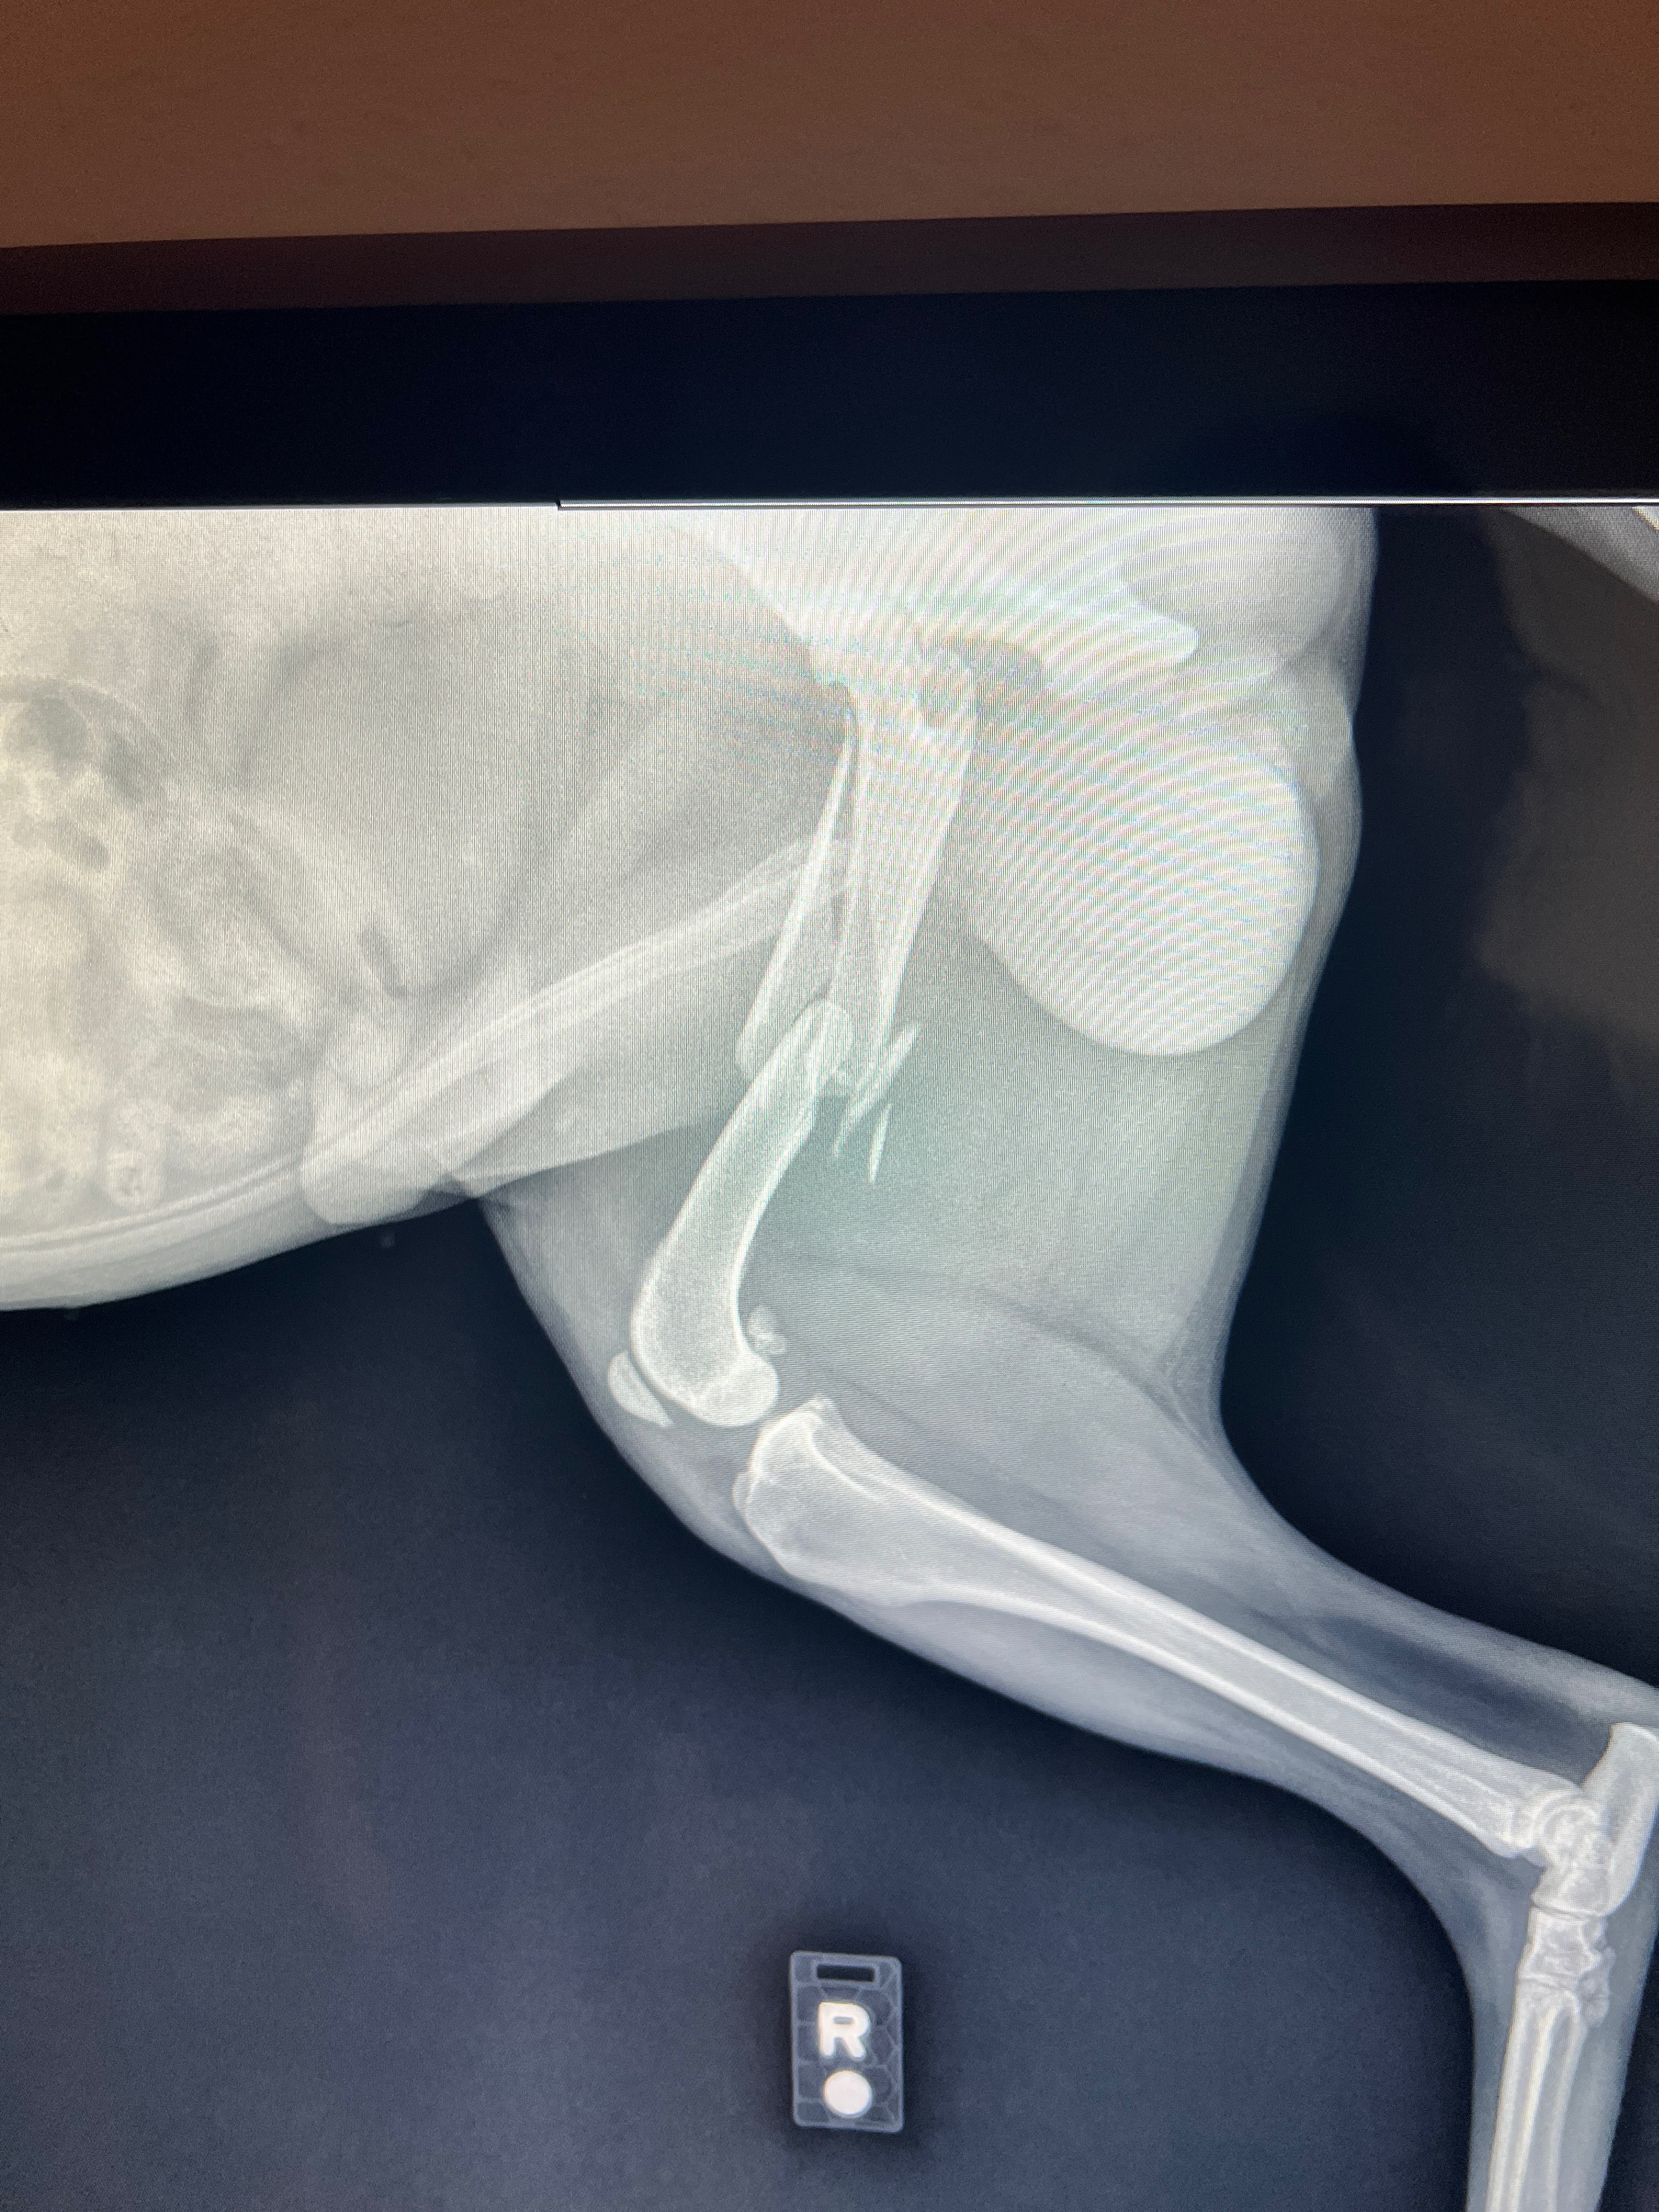

My name is Eric Pikyavit. I am raising funds for my dog (my baby dragon), Sitka Henry Pikyavit. He is nine years old and he has been by my side since he was a puppy. He is my best friend in this world and I can’t afford to help him. So I’m doing something I really don’t like to do… I’m asking for help, any help at all! He needs surgery. He jumped out of my car, and he broke his hip. I feel so bad and I know I shouldn’t blame myself, but I do because I know how he is when the window's down. He jumped out the window before, but he never rolled like he did this time. I heard a snap and saw him roll about six times. I slammed my brakes, put it in park, and he was already standing by the car with his leg in the air. I hugged him, asking him stupid questions as if he could answer me. I was going probably about 15 miles an hour around the corner.

I rushed him to the hospital in Cedar. They were able to take him in, but the doctor said the break is too complicated and I’m getting referred to St. George. I am not sure how much it’s going to cost; the doctor said it’s going to be in the thousands… So I’m hoping it doesn’t go over $3000.

This hits me hard, because when I was about ten years old, I had broken the same hip bone as Sitka’s. My right femur, and like his, the surgery was too complicated for Cedar City, I was transported to Salt Lake City. Because of how it broke and how young I was, Dr said I could never play football. So it was a major life change for me. I know his pain, I hate to know that my baby dragon is going through it. He is suffering until the surgery, which I hope is only about a week. He is a Pikyavit. He is strong. My hip broke back in the 90s and technology wasn’t at it’s best. They had to use weights to pull on my ankle to stretch my leg out, because of how it was broken, it was stretched over about a week. He will suffer but I know he will survive. I am asking and praying I get enough. I empathize, I sympathize and I’m a little traumatized. But we will prevail.